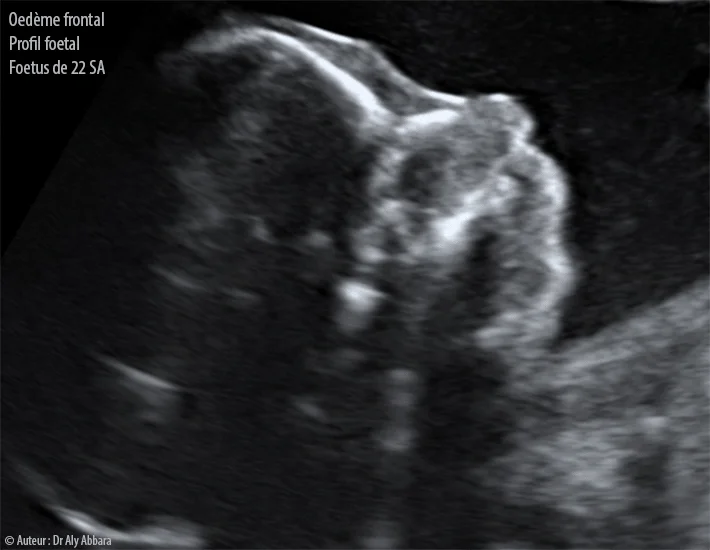

L'histoire commence au cours du troisième trimestre de grossesse. Rien ne laissait présager un drame. Pourtant, lors d'une échographie de contrôle, la sage-femme remarque une anomalie. L'inquiétude monte d'un cran lorsqu'on oriente la future maman vers le professeur Edgar Montoya, chef du pôle femme-mère-enfant au groupe hospitalier régional Mulhouse Sud-Alsace. Les examens révèlent une tumeur de 9 à 10 centimètres au niveau de la tête et du cou du fœtus. C'est énorme, surtout pour un être aussi petit.

Lors de cette consultation décisive, l'échographiste ne tarde pas à alerter l'équipe médicale. La masse est non seulement volumineuse, mais elle semble aussi très vascularisée. Pour les parents, l'annonce est un choc violent. On passe en quelques secondes de l'insouciance d'une grossesse épanouie à la perspective d'un combat pour la vie de leur enfant à naître. Le scanner et l'IRM confirment rapidement la gravité de la situation : la croissance de la tumeur est rapide et menace l'intégrité physique du fœtus.

Le diagnostic tombe : il s'agit d'une tumeur vasculaire complexe, associée à ce que l'on appelle le syndrome de Kasabach-Merritt. C'est là que le terme technique cache une réalité terrifiante. Cette tumeur ne se contente pas d'occuper de l'espace ; elle agit comme une éponge géante qui « pompe » les plaquettes sanguines du fœtus. Sans ces plaquettes, la coagulation devient impossible. Le risque d'hémorragie interne massive est permanent, et la tumeur, par sa position, comprime également l'œsophage et les voies respiratoires. En somme, le bébé est littéralement étouffé et saigne à blanc.

Pour le fœtus, les conséquences ne sont pas seulement hémorragiques. Pour alimenter cette masse tumorale gorgée de sang, le cœur du fœtus doit travailler bien plus fort que la normale. Cette surcharge cardiaque peut mener à une défaillance cardiaque anténatale. De plus, la localisation au niveau du cou comprime la trachée et l'œsophage, empêchant le fœtus de déglutir normalement le liquide amniotique et risquant une asphyxie à la naissance. Le succès du traitement repose donc sur l'administration du sirolimus, qui a montré une efficacité remarquable pour bloquer la prolifération des cellules vasculaires de la tumeur et soulager le cœur du fœtus.